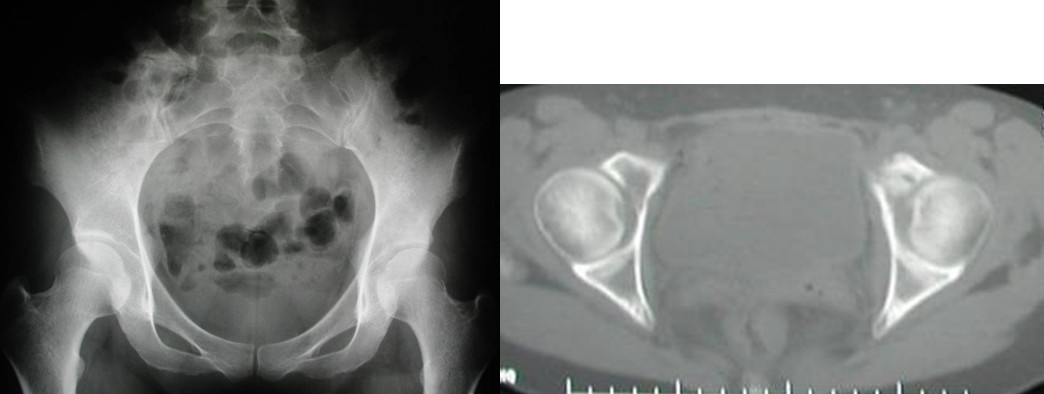

Harrington(1)根据肿瘤破坏髋臼的部位及范围,将髋臼转移癌缺损进行分型。I型:髋臼下壁骨质破坏, 内侧壁、外侧壁、髋臼上壁皮质完整;II型:髋臼内侧壁骨质破坏;III型:髋臼外侧壁、内侧壁、上壁骨质破坏; IV型:孤立性转移, 以治愈为目的的肿瘤。

本组病例中不同部位髋臼转移癌的手术方式(图1):I型:髋臼下壁骨破坏、上壁及内、外侧壁完整, 采用肿瘤刮除、普通水泥型全髋置换术。II型:髋臼内、外侧壁破坏,上壁骨质完整, 采用带翼网杯+水泥型全髋置换术。 III型:髋臼上壁及内、外侧壁均破坏,采用肿瘤刮除后、骨水泥填充髋臼上壁骨缺损,带翼网杯+水泥型全髋或组合式人工半骨盆。IV型:孤立性骨盆转移, 以治愈为目的, 采用肿瘤整块切除,组合式人工半盆置换术。

图1, 髋臼转移癌的分型示意图(北京大学人民医院)

图2,女,31岁,乳腺癌髋臼转移, Harrington I型

图3,女,55岁,肺癌髋臼转移, Harrington II型